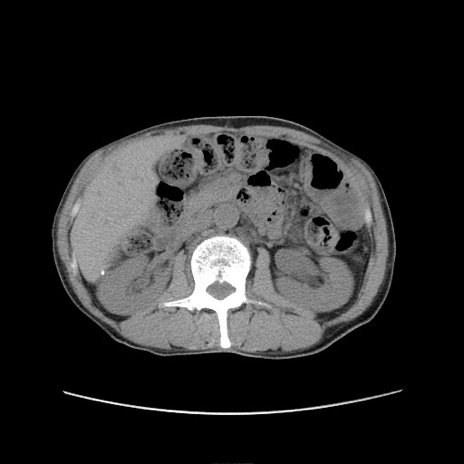

症例11(横断像)

【症例】 60歳代男性

【主訴】 下腹部痛

【現病歴】 本日夜中より下腹部痛の症状認め、受診。

【既往歴】 膀胱癌(膀胱全摘+尿管皮膚瘻術) 、胃癌術後

【身体所見】 BT 35.3℃、PR 58/min、BP 136/98mHg、腹部平坦、軟、腸蠕動音±、ストマ留置あり、左上腹部~正中部に圧痛あり、反跳痛なし。

【データ】WBC 5100、CRP0.01